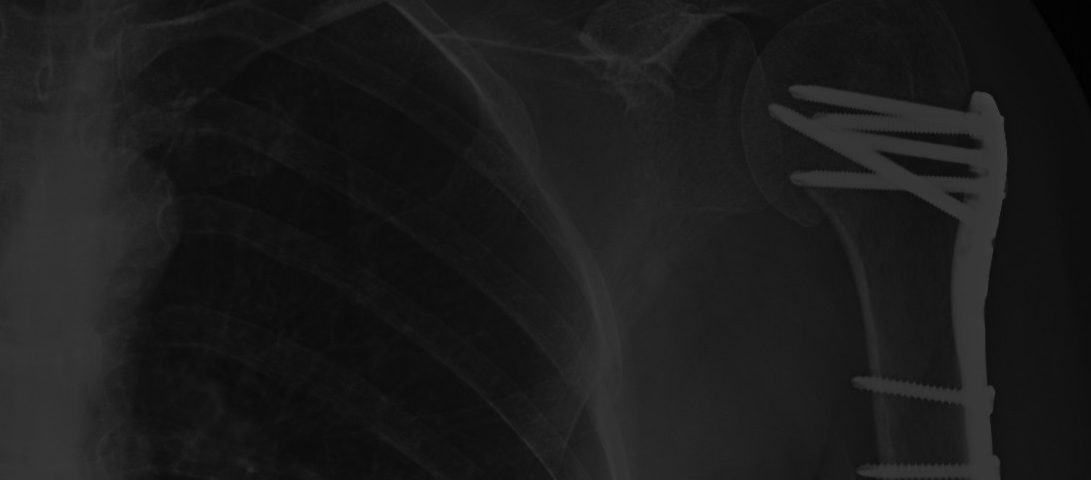

A continuación vamos a explicar la indemnización de un caso reciente de bicicleta consistente en una FRACTURA EXTREMO PROXIMAL DE HUMERO en un accidente de bicicleta causando por la imprudencia de un conductor al invadir un ceda al paso.

– Material osteosíntesis hombro izquierdo: 4 puntos

Se trata de otro caso similar por accidente de tráfico en Madrid con caída de la moto donde comenzó con un fuerte dolor en el hombro y limitación funcional. Tras la realización de pruebas complementarias se aprecio una fractura proximal de húmero derecho en 2 fragmentos con prescripción de reposo, brazo en cabestrillo, hielo y medicación. Posteriormente fue intervenida quirúrgicamente por artroscopia de hombro (bursectomia sinovectomia acromioplastia) quedando al final una serie de secuelas, que fueron indemnizadas por la compañía de seguros de la siguiente forma: